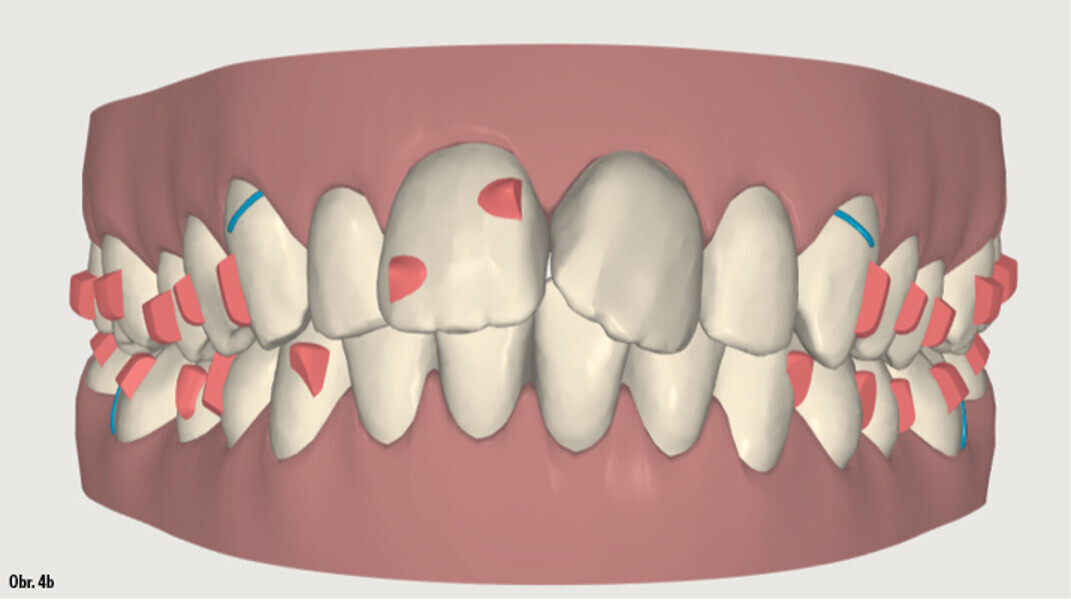

Distalizace horních molárů pomocí alignerů a cyklických sil